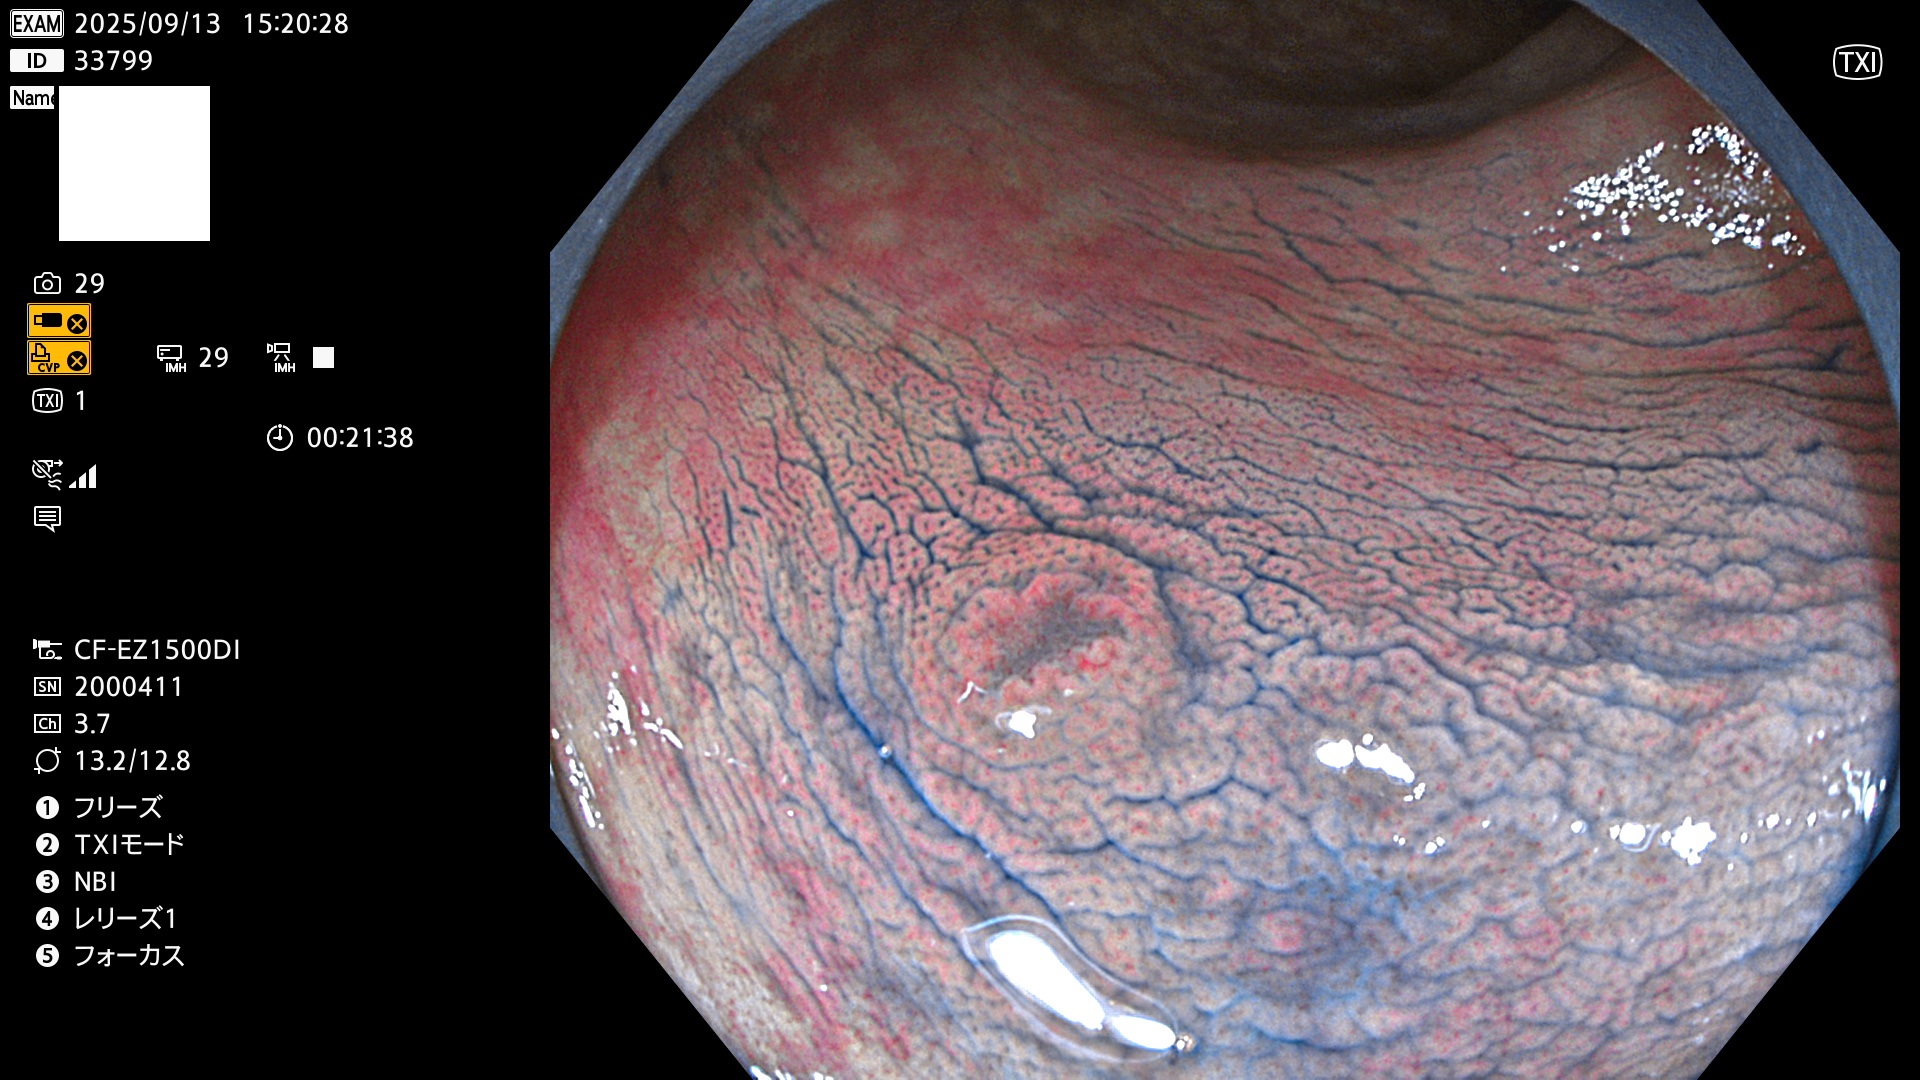

完全に平坦な物をUb、陥凹している物をUcと呼びます。Ubは認識が困難で、Ucはびらん(炎症)と紛らわしいために見落とされやすく、「内視鏡後・大腸癌」の原因になります。

専門的)Uc=De Novo癌? 内視鏡の解像度が低かった時代、このような説もありました。しかし今日の高精度内視鏡では良性の微小なUc型腺腫(APC遺伝子異常の腺腫)が日常的に見つかります。Ucこそが多段階発癌(Adenoma-Carcinoma Sequence)のMain Routeです。

専門的)細胞生物学的Ucの再定義UcをPitと形態学で定義するのは医学的には全く不毛です。Ucの本質はIntraTumor HeterogenityとTumor Dormancyが微小病変に見られる点です。これは早い腫瘍進化=ゲノム不安定性を意味します。そのような病変は隆起型でも形態によらずUcと定義すべきです。なぜなら1年後には陥凹し典型的Uc(最悪の場合NPG癌)になるからです。

2025年9月11日〜9月14日の4日間(40件)7個 (Uc_ADR=7個/40人=18%)